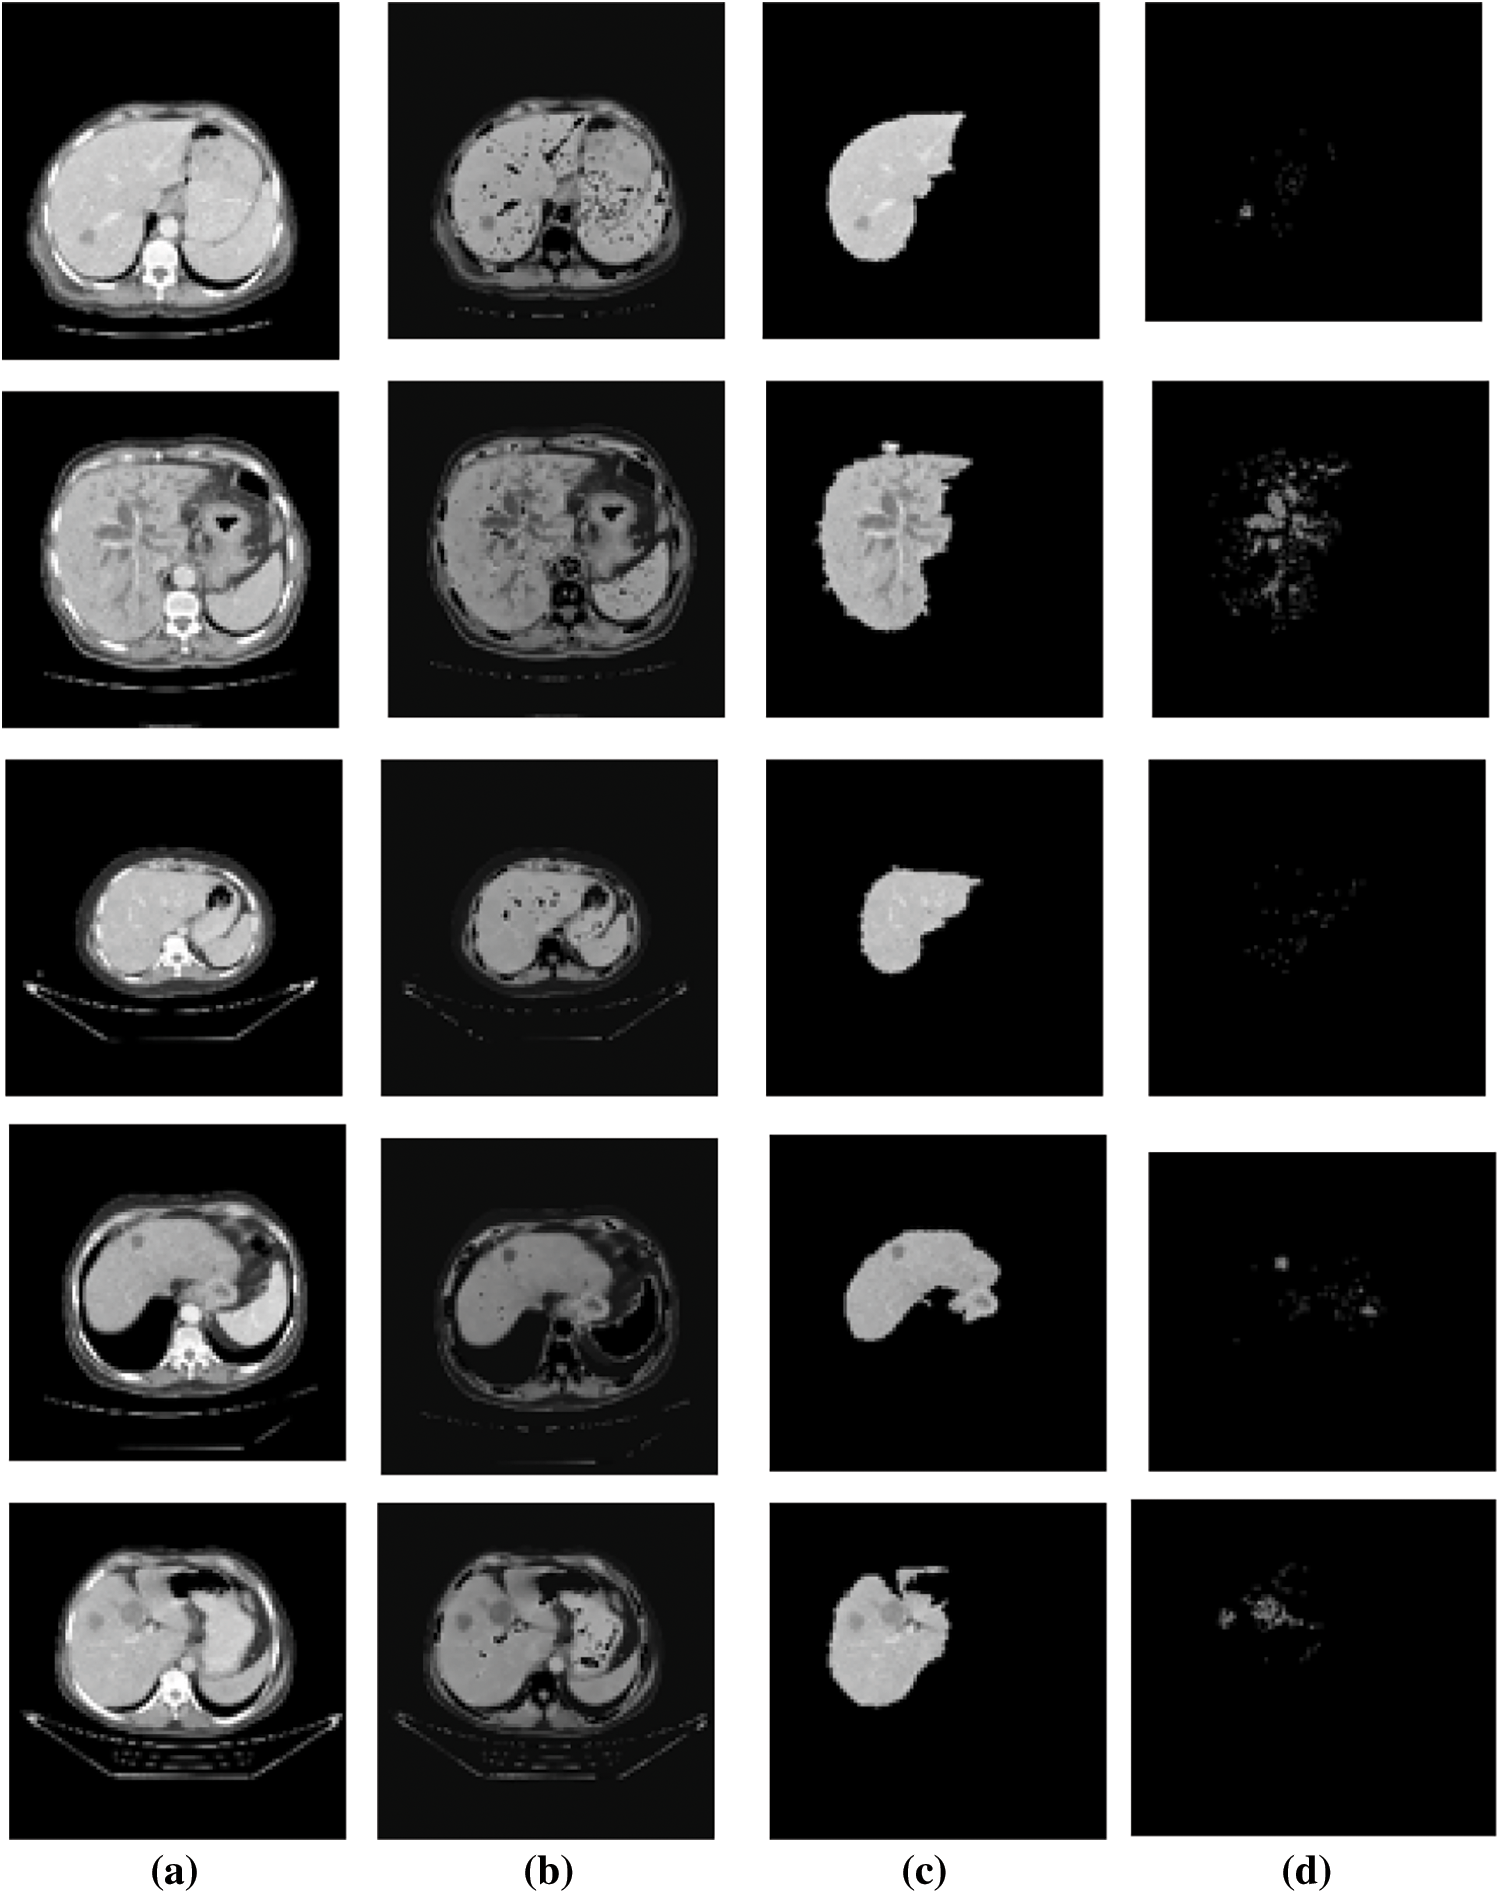

The input abdominal liver CT images are shown in Fig. 2a. The output of CE using NLM are shown in Fig. 2b.

Figure 2: Results of liver and ROI segmentation sample images (a). Input image of abdominal liver CT (b). The output of CE using NLM, (c) LTS output of the RGS algorithm, (d) The ROI segmentation results of the EM algorithm

The LTS output of the RGS algorithm is shown in Fig. 2c. The ROI segmentation results of the EM algorithm are shown in Fig. 2d. Qualitative analysis indicates the accurate segmentation performance of the method for different types of tumors and the normal images (Figs. 3 and 4). The extracted six feature values of contrast, correlation, entropy, energy, homogeneity and variance for sample ROI segmented images are tabulated in Tabs. 1 and 2.